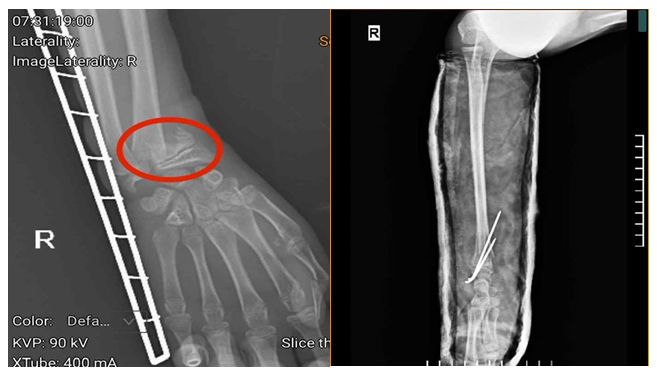

Hình ảnh phim chụp của người bệnh trước và sau khi phẫu thuật (vùng tổn thương trước phẫu thuật được khoanh đỏ).

Người bệnh vào viện trong tình trạng tay phải được cố định bằng nẹp, cẳng tay, cổ tay phải đau nhiều, sưng nề… Tại Khoa Ngoại Chấn thương và Y học Thể thao, Trung tâm Chấn thương chỉnh hình, Bệnh viện Đa khoa tỉnh Phú Thọ, người bệnh được bác sĩ khám, chỉ định thực hiện các cận lâm sàng và được chẩn đoán gãy xương cẳng tay phải.

Tuy nhiên, do thời gian tổn thương kéo dài, người bệnh bị chấn thương trước khi vào viện 3 ngày, kèm theo việc gia đình cho người bệnh bó thuốc nam nên vùng xương và cơ bị tổn thương, có hiện tượng co cứng, đặc biệt, vùng xương gãy gần với sụn, nếu không can thiệp kịp thời sẽ ảnh hưởng đến khả năng vận động sau này. Người bệnh được chỉ định phẫu thuật kết hợp xương bằng kỹ thuật C-arm với đội ngũ bác sĩ tay nghề cao, giúp nâng cao khả năng phục hồi tối đa.